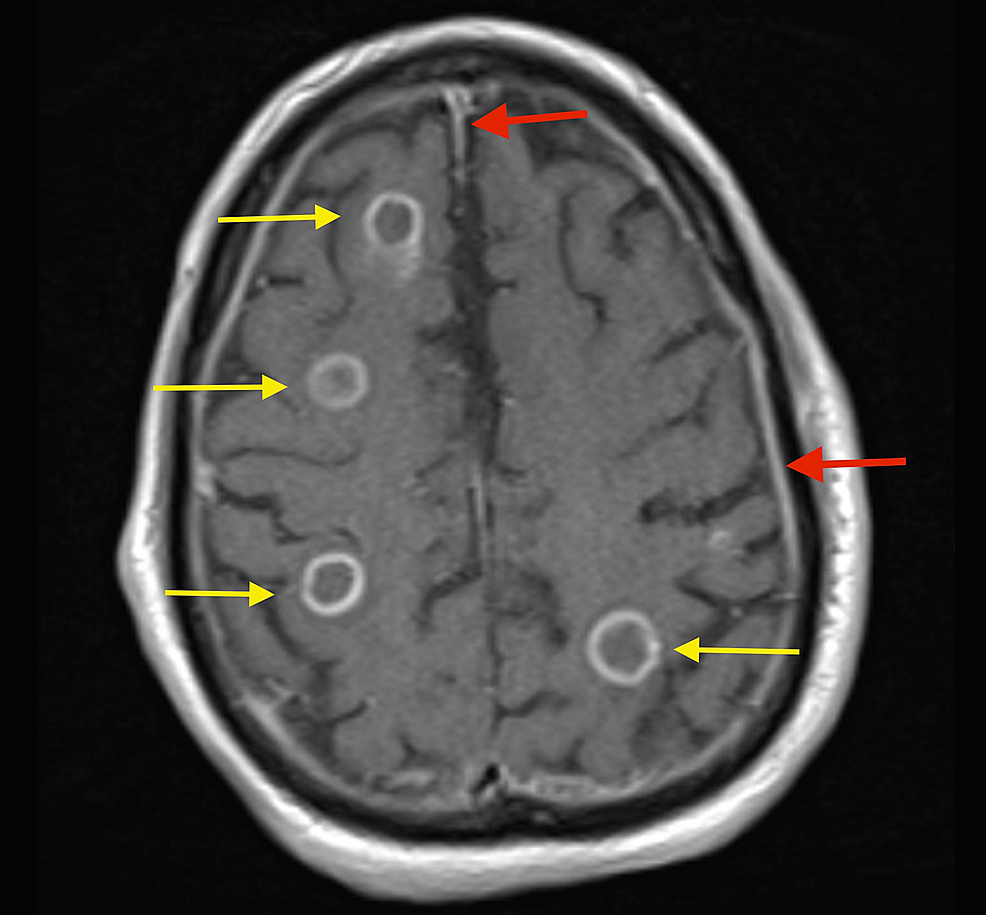

From www.cureus.com

Cureus Disseminated Central Nervous System Histoplasmosis A Case Report Radiopaedia Histoplasmosis thoracic (or pulmonary) histoplasmosis refers to pulmonary manifestations from infection with the fungus histoplasma capsulatum. histoplasmosis is an endemic mycosis caused by histoplasma capsulatum. histoplasmosis is an endemic mycosis caused by histoplasma capsulatum. the ct findings of pulmonary histoplasmosis are varied and nonspecific. the diagnosis and treatment of pulmonary histoplasmosis, as well as the pathogenesis,. Radiopaedia Histoplasmosis.

From archneur.jamanetwork.com

Isolated Central Nervous System Histoplasmosis Presenting With Ischemic Radiopaedia Histoplasmosis histoplasmosis is an endemic mycosis caused by histoplasma capsulatum. the diagnosis and treatment of pulmonary histoplasmosis, as well as the pathogenesis, clinical manifestations,. the ct findings of pulmonary histoplasmosis are varied and nonspecific. thoracic (or pulmonary) histoplasmosis refers to pulmonary manifestations from infection with the fungus histoplasma capsulatum. Pulmonary histoplasmosis is the most. histoplasmosis is. Radiopaedia Histoplasmosis.